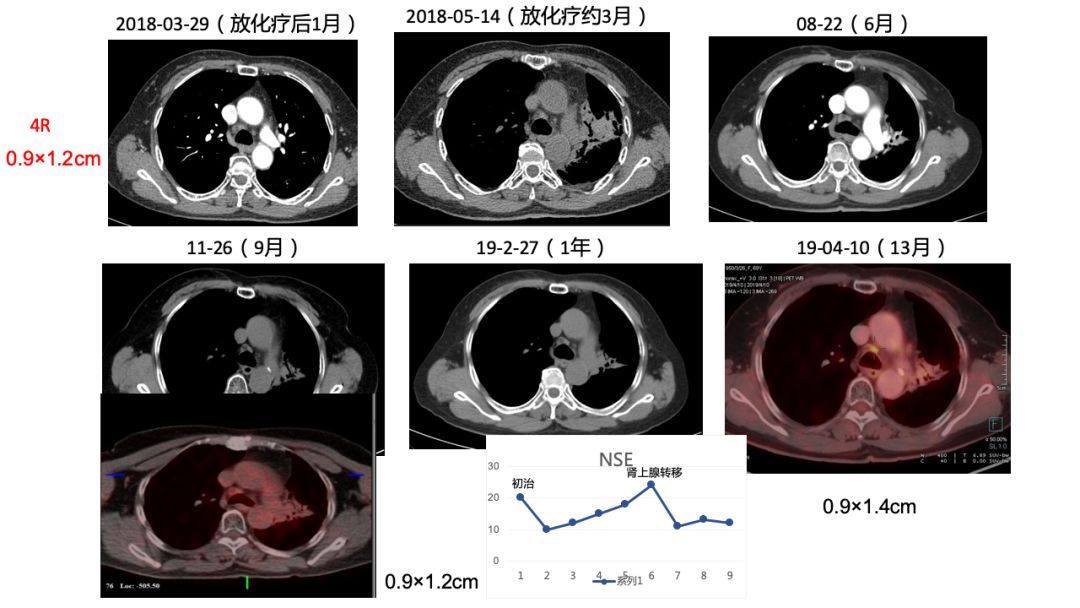

2)诊断:左下肺小细胞肺癌cT2bN2M1 IV期  PFS=12月。

3)原发灶+8组LN(放疗区) PR 疗效。

4)肾上腺转移术后。

5)4R,10R组LN(非放疗区)1年来随访大小未见变化,4R实性程度增高,代谢增高2倍。

初诊时4R,10R LN增大,PET考虑炎症,未行放疗,随访期间淋巴结大小无变化,NSE稳定正常,建议观察,3个月后复查CT。